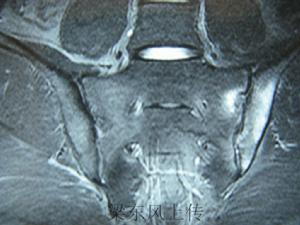

對於臨床可疑病例,而X線片尚未顯示明確的或Ⅱ級以上的雙側骶髂關節炎改變者,應該採用計算機斷層(CT)檢查。該技術的優點還在於假陽性少。但是,由於骶髂關節解剖學的上部為韌帶,因其附著引起影像學上的關節間隙不規則和增寬,給判斷帶來困難。另外,類似於關節間隙狹窄和糜爛的骶髂關節髂骨部分的軟骨下老化是一自然現象,不應該視為異常。見圖2。